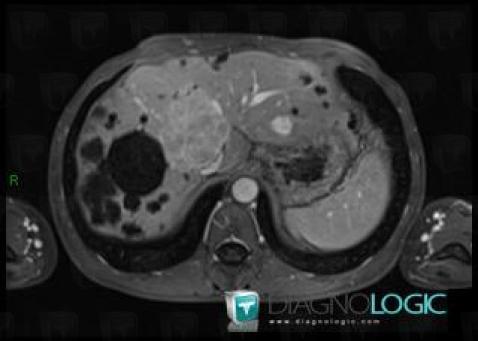

Polykystose rénale, Foie, IRM

Voici les informations spécifiques à l'image clé ci dessus:

- Diagnostic Polykystose rénale, Localisation(s) Foie, comportant les gammes Lésion hépatique en hypersignal T2

- Diagnostic Polykystose rénale (lié à Polykystose hépatique), Localisation(s) Foie, comportant les gammes Lésion hépatique kystique